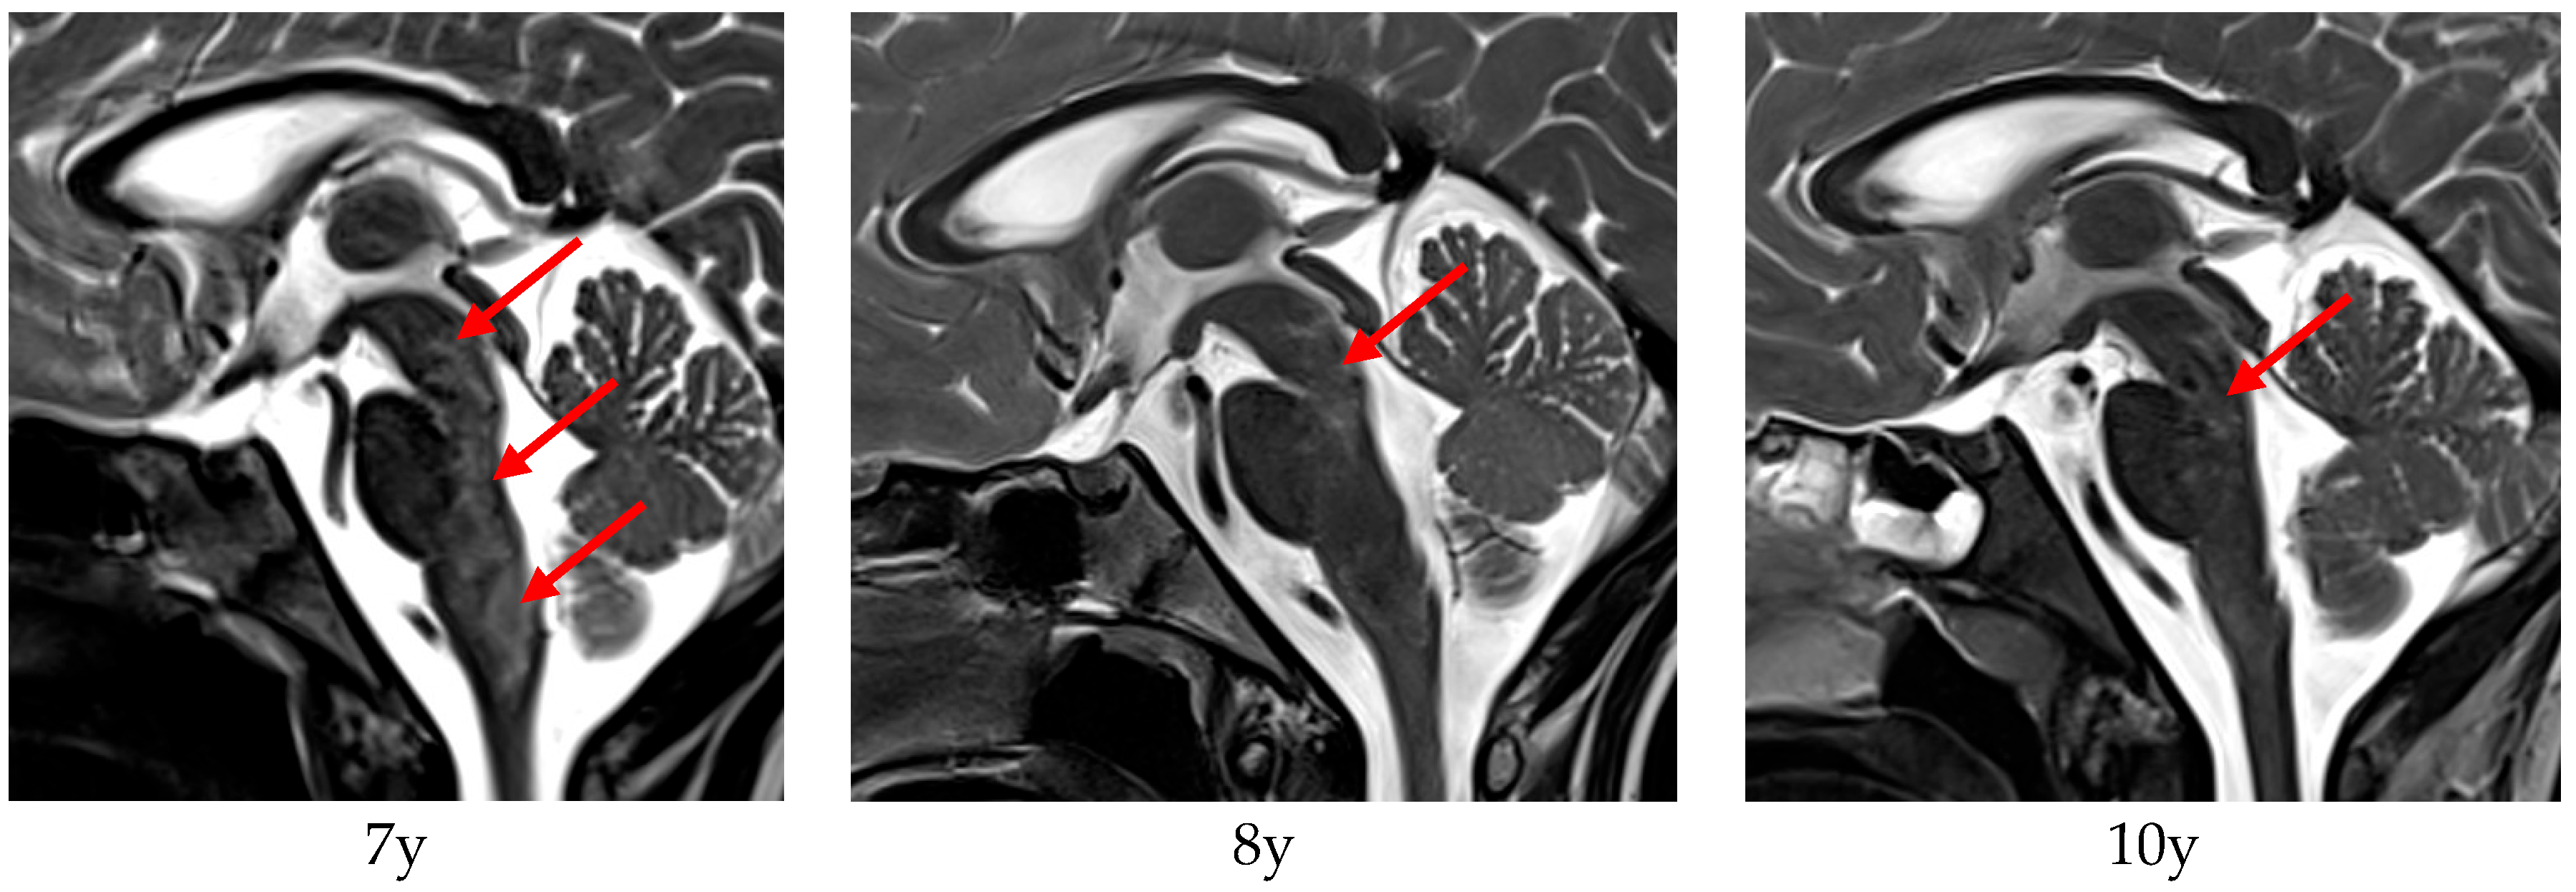

Patient 9 showed fine motor skills dysfunction and balance issues beginning at the age of two years. Vomiting was observed at the age of six years and suspended after a short time, but dysphagia and weight loss occurred. Speech became dysarthric and nasal. Brain MRI showed periventricular cystic lesions and T2 signal alterations along the posterior brainstem, considered as a post-infectious rhombencephalitis. Pulse therapy with immunoglobulins and steroid lead to an improvement of the general condition and of eating and speaking. The diagnosis of AxD was confirmed at the age of seven years. At the age of almost eight years, the patient experienced deterioration in her general condition (dysphagia, dysarthria, sleep apnoea) and was hospitalized for another therapy trial with immunoglobulins and steroids, again with subsequent clinical improvements afterwards. Brain MRI revealed typical signs of AxD. Corresponding MRI images are shown in Figure 1, revealing a decrease in the brainstem T2 hyperintensities over time, correlating with the improved clinical condition between the onset of disease and last examination. In the most recent examination, the patient was in a stable clinical state with only minor symptoms.

Patient 9 demonstrated not only clinical improvement but also radiological signs of decreased signal abnormalities of the medulla oblongata on MRI. To our knowledge, this has not been previously reported in any other case of AxD. However, as MRI scans were not performed immediately before and after steroid and immunoglobulin pulse therapy, it remains unclear whether the observed improvements were solely due to the immunomodulatory treatment or if they might reflect spontaneous fluctuations.

Figure 1. cMRI (T2) of patient 9 at the age of 7 years (1 month after first immunoglobulin and steroid pulse therapy), 8 years, and 10 years. The edematous T2 hyperintense brainstem lesions (red arrows) at the age of 7 years improved over time, correlating to clinical condition of the patient, who started with a massive loss of weight and dysarthria at onset of disease, evolving to a progressively stable condition.